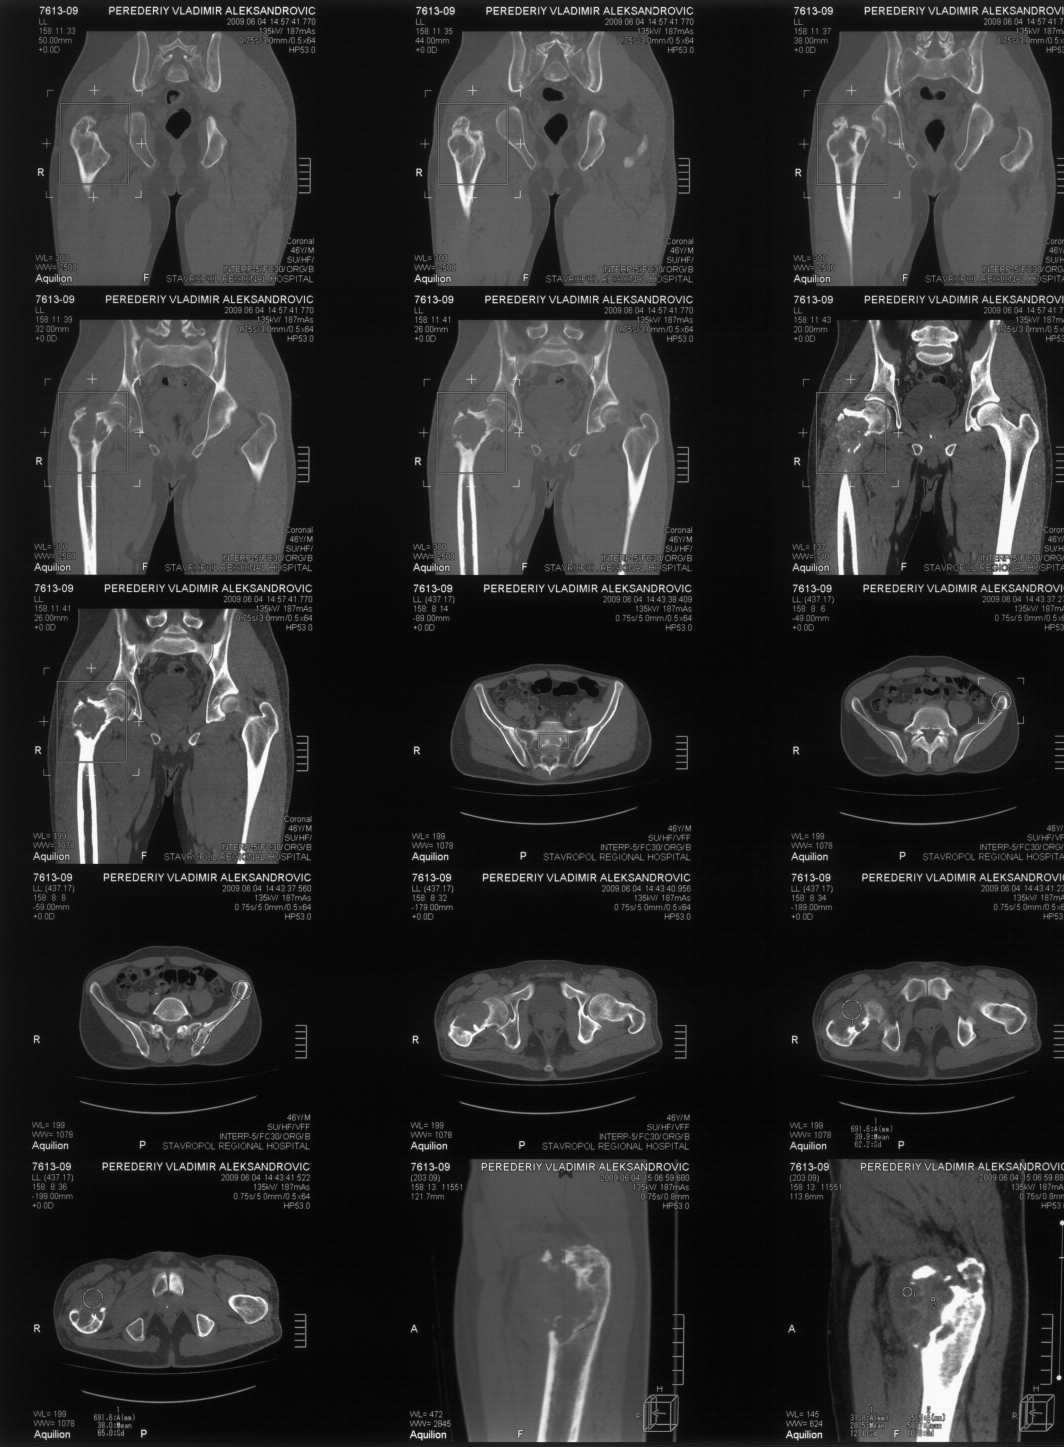

Диагноз: Ангиосаркома проксимального отдела правой бедренной кости. Патологический перелом шейки бедренной кости. Множественные метастазы в легкие, позвоночник, ребра, кости таза.

Считает себя больным с 2005 года, когда впервые появились боли в правом тазобедренном суставе с иррадиацией в поясничную область. Лечился по месту жительства по поводу поясничного остеохондроза, люмбоишиалгии. Отмечает постепенное усиление болей в области правого тазобедренного сустава. С августа 2007 года появилась хромота. В 2008 году была выполнена рентгенография тазобедренного сустава, выявлен патологический очаг в проксимальном отделе бедренной кости. Консультирован онкологом. Обследовался стационарно в травматолого-ортопедическом отделении №1 ГУЗ «СККЦ СВМП». Была выполнена операционная биопсия. Заключение: «наиболее вероятна картина гемангиоэндотелиомы с явлениями пролиферации и атипии». Для дальнейшего лечения был направлен в РОНЦ им. Н.Н.Блохина РАМН. Повторно была выполнена операционная биопсия с иммуногистохимическим исследованием материала. Заключение: «морфологическая картина более всего соответствует ангиосаркоме». Получил курс лучевой терапии. Планировалась повторная госпитализация для органосохраняющего оперативного лечения. Однако до настоящего времени госпитализация не состоялась.

31.05.09 упал дома с высоты собственного роста. Появились сильные боли в правом тазобедренном суставе. Самостоятельно обратился в ГУЗ «СККЦ СВМП». При клиническом обследовании и рентгенографии был диагностирован патологический перелом шейки бедренной кости.Объективно:

Интересно как онкологи оценивают вероятную подолжительность жизни, если более полугода, то наверное можно предложить биполярный онкологический протез. Для обсуждения не хватает снимков бедра на всю длину, и более подробной КТ ацетабулюма.

Судя по КТ опухоль кроме шейки захватила большой трохантер и частично головку бедра. На мой взгляд, даже самое удачное расположенние винтов гвоздя не позволит больному полностью наступать на ногу. Протез же позволит больному максимально улучшить качество оставшейся жизни с раннего послеоперационного периода.